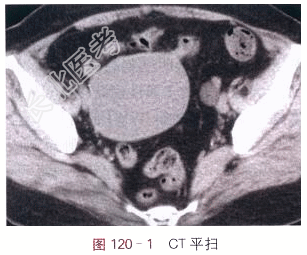

- [材料题] 女,78岁,自觉腹部肿块3月余。体格检查:右下腹肿块,边界清,质地软。影像学资料如图120-1~图120-2所示。

读片分析:右侧附件区见直径8cm类圆形囊性灶,密度均匀,囊内未见分隔;囊壁薄,未见壁结节,未见异常强化。左侧附件区也见直径1.5cm类圆形囊性灶,密度均匀,未见强化。